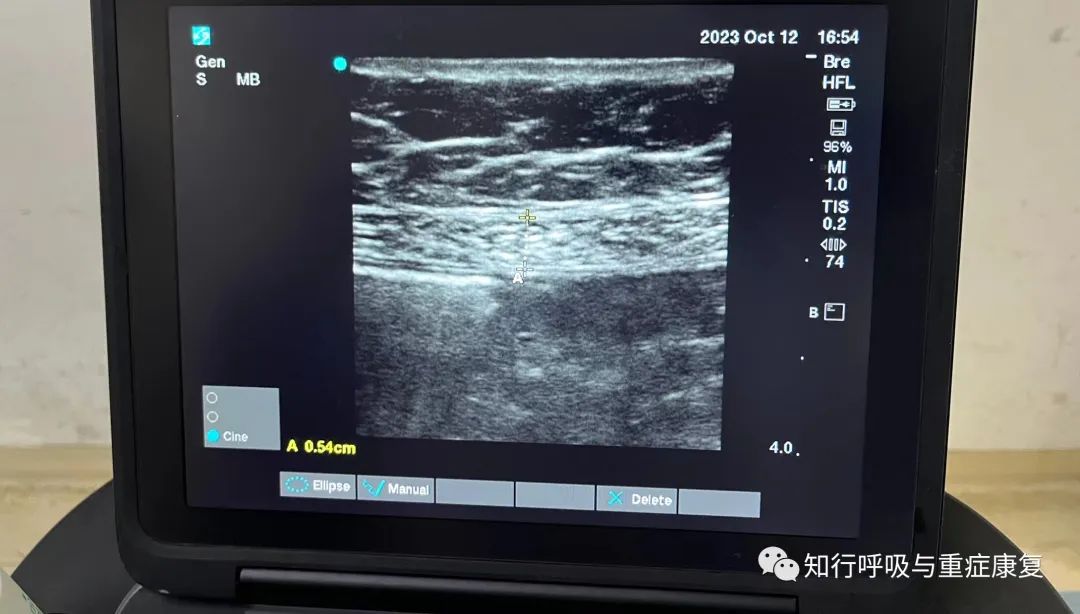

对于腹直肌(RA), 探头放置在脐上方2-3厘米 , 距离中线2-3厘米 。

图5 机械通气患者的腹直肌· 2.3 肌肉厚度·